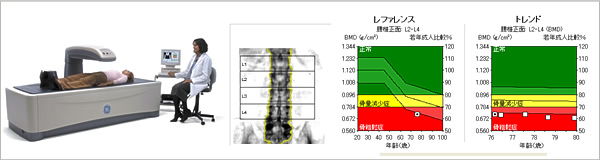

現在、様々な骨量測定法がありますが、最も信頼の高い骨量測定法であると推奨されているものにDEXA (Dual Energy X-ray Absorptiometry) 法を用いた骨密度測定装置があります。当院ではこのDEXA法を用いた骨密度測定装置(PRODIGY:GE横河メディカル社製)で腰椎と大腿骨を測定し、高精度を保ちながら、高速撮影、被ばく量の低減を実現した検査を行っています。